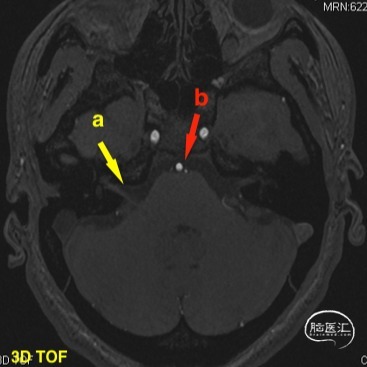

头颅MR(2021-07-23),面听神经复合体未见明显血管压迫。

a 黄色箭头为患侧面听神经复合体 b 红色箭头为动脉成像